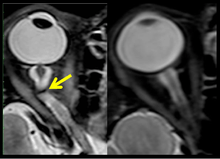

The sixth case of visual changes of an ISS astronaut was reported after return to Earth from a 6-month mission. When he noticed that his far vision was clearer through his reading glasses. A fundus examination performed 3 weeks postflight documented a grade 1 nasal optic-disc edema in the right eye only. There was no evidence of disc edema in the left eye or choroidal folds in either eye (Figure 13). MRI of the brain and eyes days postflight revealed bilateral flattening of the posterior globe, right greater than left, and a mildly distended right optic nerve sheath. There was also evidence of optic-disc edema in the right eye. A fundus examination postflight revealed a "new onset" cotton-wool spot in the left eye. This was not observed in the fundus photographs taken 3 weeks postflight.[3]

The seventh case of visual changes associated with spaceflight is significant in that it was eventually treated postflight. Approximately 2 months into the ISS mission, the astronaut reported a progressive decrease in his near and far acuity in both eyes. The ISS cabin pressure, CO2 and O2 levels were reported to be within normal operating limits and the astronaut was not exposed to any toxic substances. He never experienced losses in subjective best-corrected acuity, color vision or stereopsis. A fundus examination revealed a grade 1 bilateral optic-disc edema and choroidal folds (Figure 15).[3]